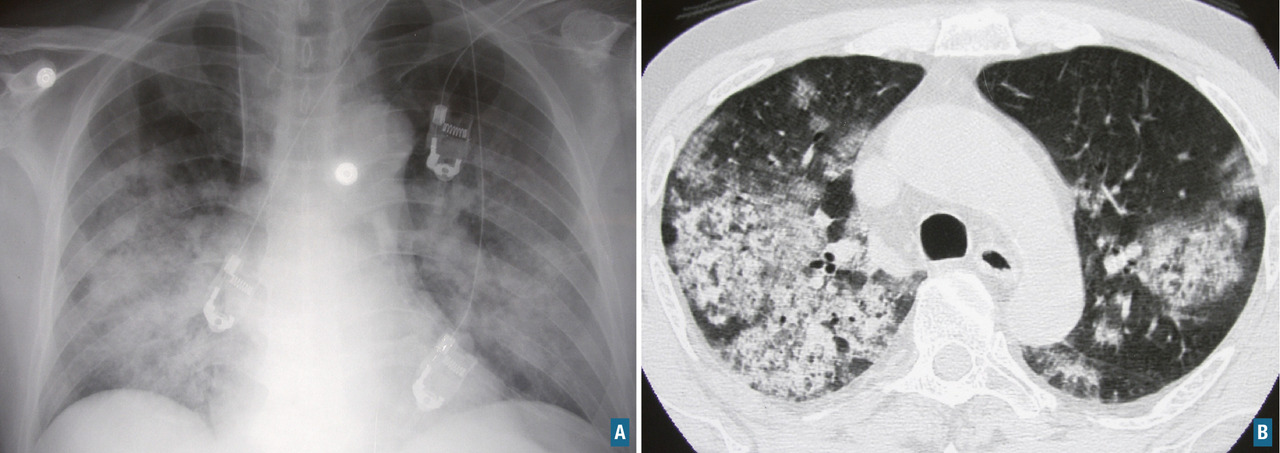

L’atteinte pulmonaire est variable : infiltrats alvéolaires, aspect en verre dépoli, nodules multiples excavés (fig. 9). L’hémorragie alvéolaire, complication majeure mais rare de la granulomatose avec polyangéite, se produit au niveau de la circulation pulmonaire distale entraînant un comblement alvéolaire (fig. 10). Elle se manifeste par une hémoptysie, une dyspnée, une anémie, des opacités diffuses alvéolaires et un liquide hémorragique au lavage bronchoalvéolaire (LBA). Des sténoses trachéo­bronchiques sont possibles.

L’atteinte rénale est glomérulaire pauci-immune (absence de dépôts significatifs d’immunoglobulines ou de complément dans les glomérules), nécrosante, segmentaire et focale, associée à une prolifération extra­capillaire (fig. 11) avec parfois des granulomes juxtaglomérulaires ou interstitiels. Elle se manifeste par une glomérulonéphrite rapidement progressive (tableau 13) caractérisée par la survenue en deux à huit semaines d’une protéinurie variable, d’une hématurie microscopique et d’une insuffisance rénale rapidement progressive. Elle est confirmée par la biopsie rénale et nécessite l’instauration rapide d’un traitement.